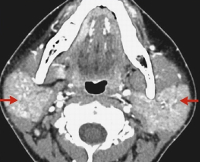

Эпидемический паротит или свинка - легкое вирусное заболевание, проявляющееся в виде опухания слюнных желез с одной или обеих сторон нижней челюсти.

Вирус вызывает опухание одной или обеих околоушных слюнных желез, которые расположены ниже и перед слуховым проходом. При поражении обеих желез ребенок приобретает характерный вид хомяка. У мальчиков-подростков и юношей (примерно у 1 из 4) этот вирус может вызвать болезненное воспаление одного или обоих яичек, в редких случаях следствием болезни может быть бесплодие.